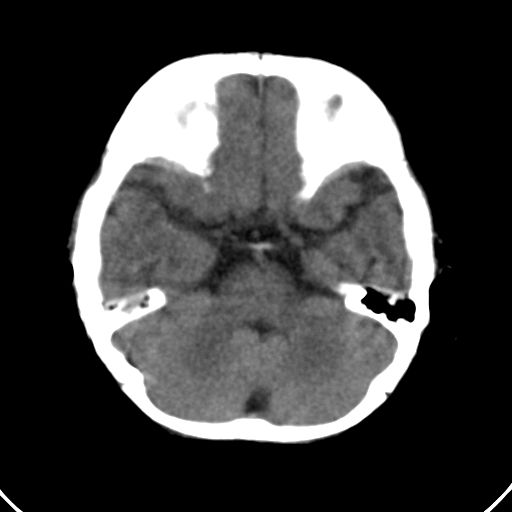

男,10月,足月剖腹产,无缺氧病史,当时评分均正常,学走路时脚后跟不着地!

小孩子片子,看得少,请各位老师看看有问题没?

未见明显异常。

外部性脑积水

考虑外部性脑积水

双侧脑鹅叶发育不良.

轻度脑外脑积水表现.